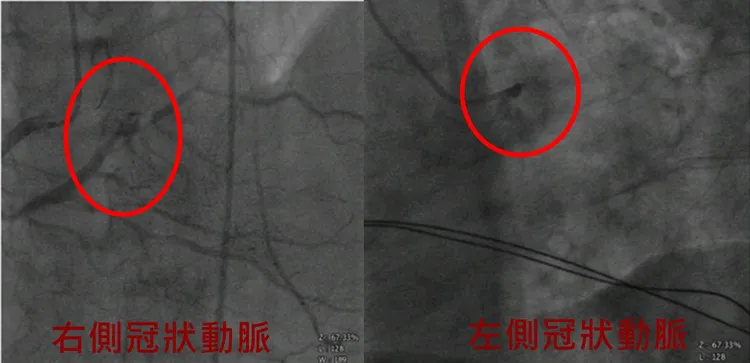

童綜合醫院表示,當患者送抵急診後,醫護人員黃不停施以CPR急救,並協助心臟外科與葉克膜團隊直接在急診進行葉克膜置放,迅速讓患者恢復自主呼吸心跳,經心導管檢查確認雙側冠狀動脈嚴重阻塞導致急性心肌梗塞,再進行緊急冠狀動脈繞道手術,住院19天後出院返家,目前恢復良好且回診檢查心臟功能逐漸恢復。

患者雙側冠狀動脈嚴重阻塞。院方提供